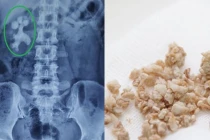

Những sai lầm trong ăn uống khiến nguy cơ mắc sỏi thận tăng cao

Nhiễm trùng đường tiết niệu, đau lưng, tiểu són, tiểu dắt, tiểu ra máu, đau đớn khi đi tiểu,… là những hậu quả do sỏi thận gây ra. Nguyên nhân sỏi thận lại đến từ chính những sai lầm trong ăn uống của nhiều người.